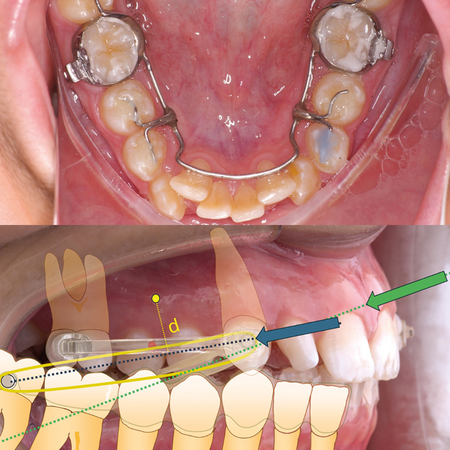

INTRODUÇÃO: O gerenciamento dos espaços das agenesias dentárias é frequentemente relatado como um desafio adicional para o tratamento ortodôntico e, quando associado à má oclusão esquelética, torna o tratamento mais complexo. OBJETIVO: Neste relato de caso, objetivou-se apresentar um tratamento ortopédico seguido de tratamento ortodôntico compensatório de um paciente Classe III esquelética severa com agenesia dentária múltipla. RELATO DE CASO: Paciente do sexo masculino, com 14 anos de idade, teve um plano de tratamento atípico, inicialmente tratado com máscara facial...

INTRODUÇÃO: O gerenciamento dos espaços das agenesias dentárias é frequentemente relatado como um desafio adicional para o tratamento ortodôntico e, quando associado à má oclusão esquelética, torna o tratamento mais complexo. OBJETIVO: Neste relato de caso, objetivou-se apresentar um tratamento ortopédico seguido de tratamento ortodôntico compensatório de um paciente Classe III esquelética severa com agenesia dentária múltipla. RELATO DE CASO: Paciente do sexo masculino, com...

INTRODUCTION: Space management of tooth agenesis is often reported as an additional challenge for orthodontic treatment and, when associated with skeletal malocclusion, makes the treatment more complex. OBJECTIVE: The objective of this case report was to present an orthopedic treatment followed by comprehensive orthodontic treatment of a severe skeletal Class III patient with multiple tooth agenesis. CASE REPORT: A 14-year-old male had an atypical treatment plan, starting with facemask...